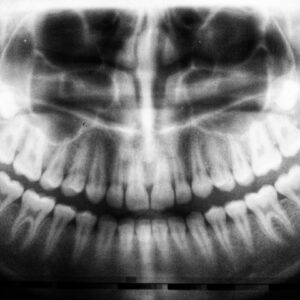

Photo Dental X-ray

Tooth Decay Antalya

Tooth decay, also known as dental caries, is a prevalent oral health issue that affects individuals of all ages in Antalya. It occurs when the hard surface of your teeth…

Tooth Decay At Gum

Tooth decay at the gum line is a common dental issue that can affect anyone, regardless of age or oral hygiene habits. This type of decay occurs when the protective…

Tooth Decay At Gum Line

Tooth decay at the gum line is a common dental issue that can lead to significant oral health problems if left untreated. This type of decay occurs when the protective…

Tooth Decay At Gum Line Pictures

Tooth decay at the gum line is a common dental issue that occurs when the protective enamel of your teeth is compromised, leading to cavities or decay specifically near the…